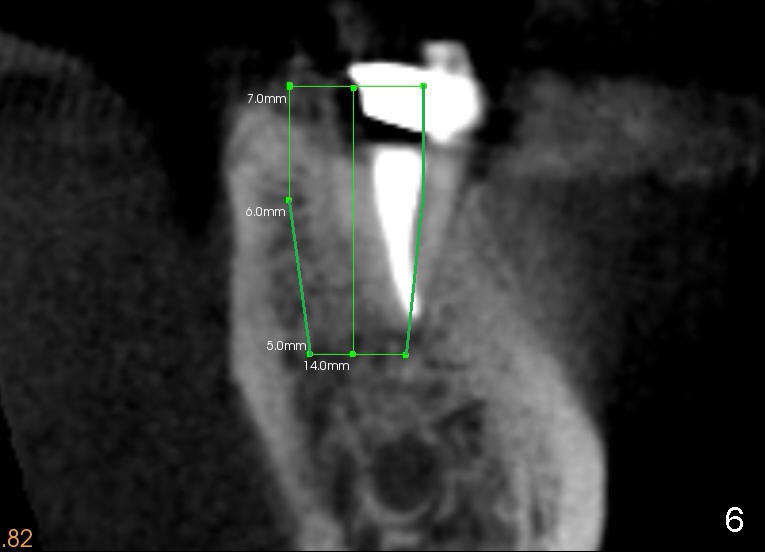

With planning and effort, the final osteotomy is in the middle of the socket (Fig.5). The implant is placed in restoratively favorable position (Fig.6).